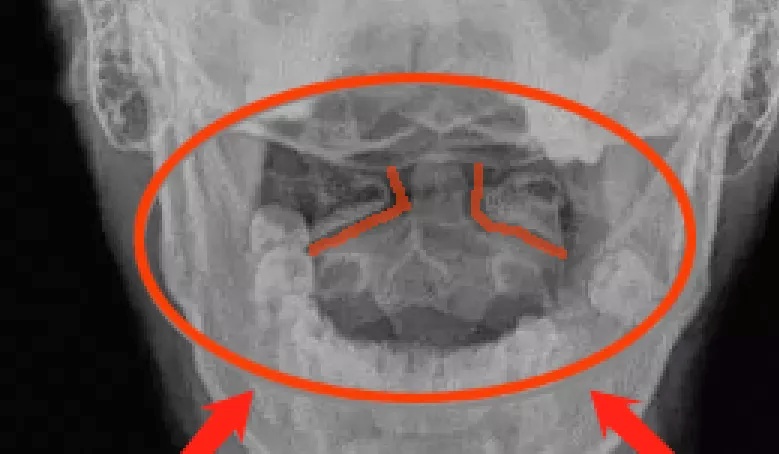

开口位X光片

这类小孩子在检查时,一定要做个开口位的X光片检查,就很容易发现寰齿侧间隙和寰枢关节间隙左右不对称。

寰齿侧间隙左右不对称